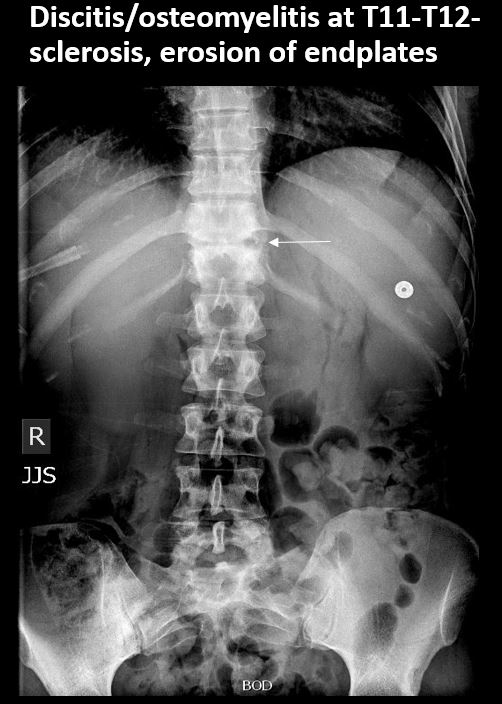

There is a lytic, blastic, or destructive lesion of the spine, pelvis, femurs, or ribs. |

No | NA |

There is abnormality of the discs, SI or hip joints, or pubic symphysis or other incidental abnormality of the pelvis. |